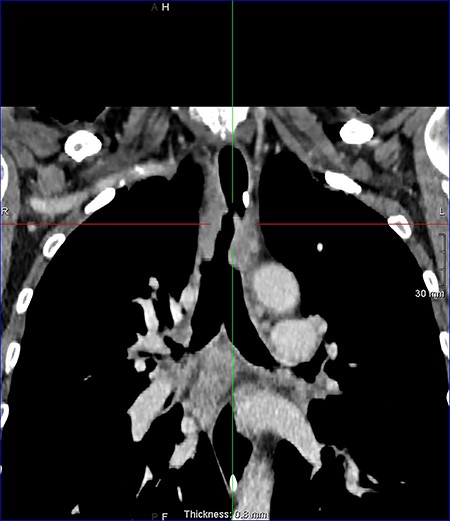

On examination, the patient had no obvious abnormality in the valve puncture. The stoma site was normal except for some crusting around the edges. A marked abnormality on the tracheal wall ~6 cm inferior to the stoma site was revealed, through a flexible nasal endoscopic examination. The abnormality was later confirmed to be a TOF. The patient underwent a computed tomography (CT) scan to delineate the surrounding anatomy as to facilitate the planning of the surgery (Figs 2–4).

Sagital reconstruction post contrast CT neck and thorax images with 4 mm defect/tracheoesophageal fistula located 8–9 cm from tracheostomy level and 12 cm proximal to the carina.